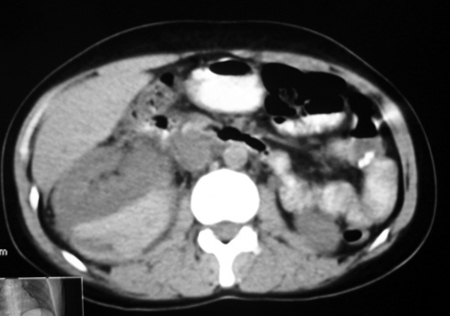

以下是引用bmw011在2009-4-23 13:28:00的发言:[br]考虑右肾包膜下血肿。

以下是引用卜一在2009-4-23 15:43:00的发言:[br]考虑右肾包膜下血肿,不排除占位病变伴出血可能,建议进一步检查。